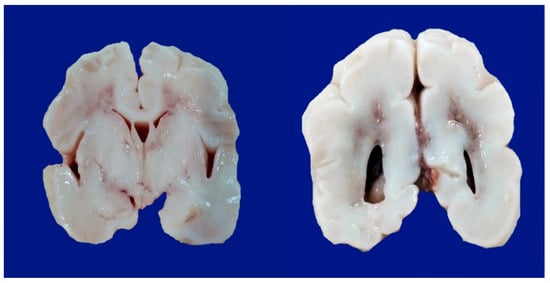

8. Neonatal Hypoxic–Ischemic Encephalopathy: Clinical Aspects

- Parasagittal injury of the cerebral cortex, in subcortical white matter in the lateral convection of the superior-medial orientation, in the posterior–anterior direction.

- Periventricular leukomalacia with necrosis in the subcortical white matter of the hemisphere, including descending motor fibers, optical radiations, and association fibers.

- Focal and multifocal necrotic ischemia in the cerebral cortex and subcortical necrosis in white matter, mainly unilateral with a vascular distribution.